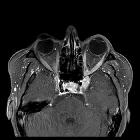

cavernous sinus mass

sinus mass • Meckel cave meningioma - Ganzer Fall bei Radiopaedia

sinus mass • Trigeminal schwannoma - Ganzer Fall bei Radiopaedia

sinus mass • Intracranial aneurysm - Ganzer Fall bei Radiopaedia

sinus mass • Chondrosarcoma - sphenoid wing - Ganzer Fall bei Radiopaedia

sinus mass • Tolosa-Hunt syndrome - Ganzer Fall bei Radiopaedia

sinus mass • Neurolymphomatosis - Ganzer Fall bei Radiopaedia

sinus hemangioma • Cavernous sinus hemangioma (huge) - Ganzer Fall bei Radiopaedia

• Cavernous sinus meningioma - Ganzer Fall bei Radiopaedia